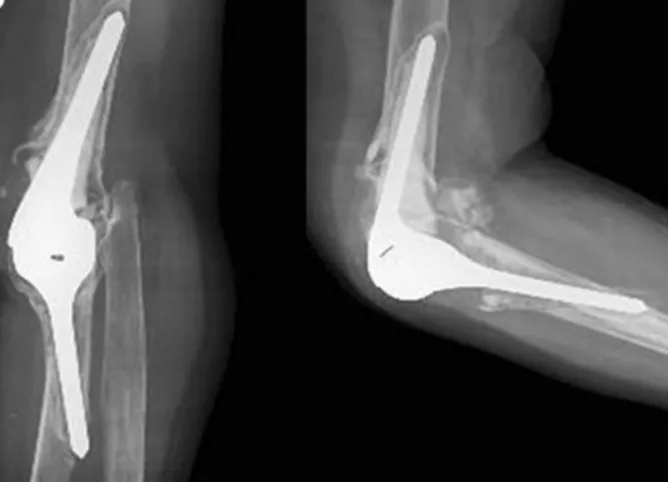

- Definition: Surgical replacement of elbow joint with artificial components (prosthesis).

- Total Elbow Arthroplasty (TEA): Replaces both humeral and ulnar articular surfaces.

- Linked (Semi-constrained):

- For poor bone stock, ligamentous insufficiency, older/low-demand patients, revision cases.

- Provides inherent stability.

- Most common.